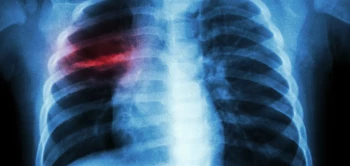

Preventieve vaccinatie is één van de meest doeltreffende en kostenbesparende strategieën in de gezondheidszorg. Voor de bestrijding van tuberculose (tbc) hebben we dit jaar op de kop af, al een eeuw het zogeheten BCG-vaccin tot onze beschikking. Het bespaart daarmee veel ellende en vooral kinderlevens. Maar deze 'jubilaris' faalt helaas bij het terugdringen van ernstige longtuberculose in (jong-)volwassenen, waardoor tbc alleen het huidige covid boven zich vindt in de lijst van meest bedreigende infectieziekten ter wereld.

In eerder onderzoek hadden wetenschappers van BPRC al vastgesteld dat vaccinatie met BCG via de luchtwegen (mucosaal) betere bescherming biedt dan wanneer het, zoals gebruikelijk via de huid wordt ingespoten. Daarbij bleek de immuniteit, met name in de luchtwegen een setje unieke eigenschappen te hebben die zouden kunnen verklaren waarom die mucosale vaccinatiestrategie beter blijkt te werken.